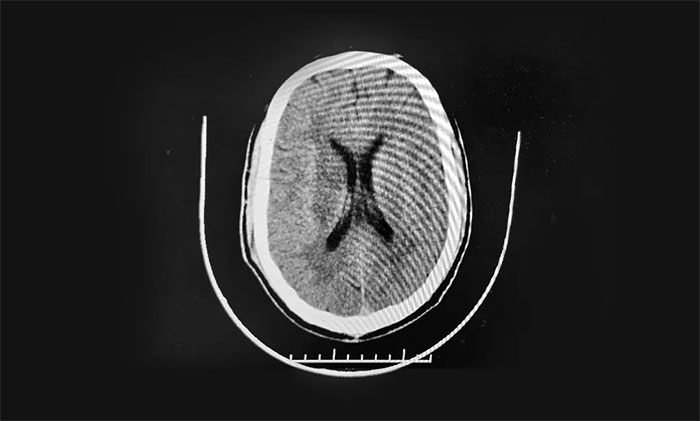

▲ 右侧基底节脑梗死

患者既往有糖尿病病史7年,血糖控制在13毫摩尔每升。高血压3级极高危,收缩压最高180毫米汞柱,舒张压最高100毫米汞柱。

入院时,患者左上肢近端肌力2级,左上肢远端肌力0级,左下肢近端肌力2级,左侧下肢远端肌力0级,肌张力正常。NIHSS评分11分。

头颅CTA示:左侧颈内动脉C4-5段、右侧颈内动脉C5段钙化斑块形成。右侧大脑中动脉M1段及左侧大脑中动脉M2段重度狭窄。头颅CTP示:两侧幕上脑微循环不良:慢期缺血、血容量CBV下降为主(右基底节区较显)。

综合相关检查,患者确诊:右侧基底节区梗死。